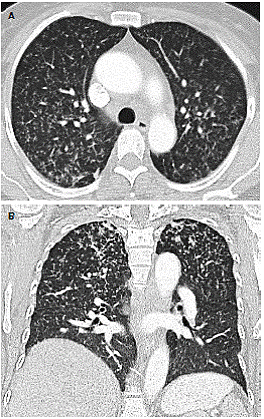

At the moment of hospitalization, the patient did not present any sign of rheumatoid arthritis activity (Clinical Diseases Activity Index: 0). A computed tomography (CT) scan of the brain was done showing a hypodense basal right lesion associated with vasogenic edema in the left frontal lobe upon which extension studies were requested. Brain magnetic resonance imaging showed supraand infratentorial lesions highly suggestive of caseous granulomas (figure 1). A chest CT showed centrilobular micronodules with soft tissue density and branched centrilobular linear densities (figure 2). Abdomino-pelvic CT showed iliac mesenteric and retroperitoneal lymphadenopathy and wall thickening of the distal ileum (figure 3), which is highly suggestive of tuberculosis as a first diagnostic possibility. Lymph node biopsy reported granulomatous lymphadenitis with acid-alcohol resistant bacilli, thus confirming the diagnosis.